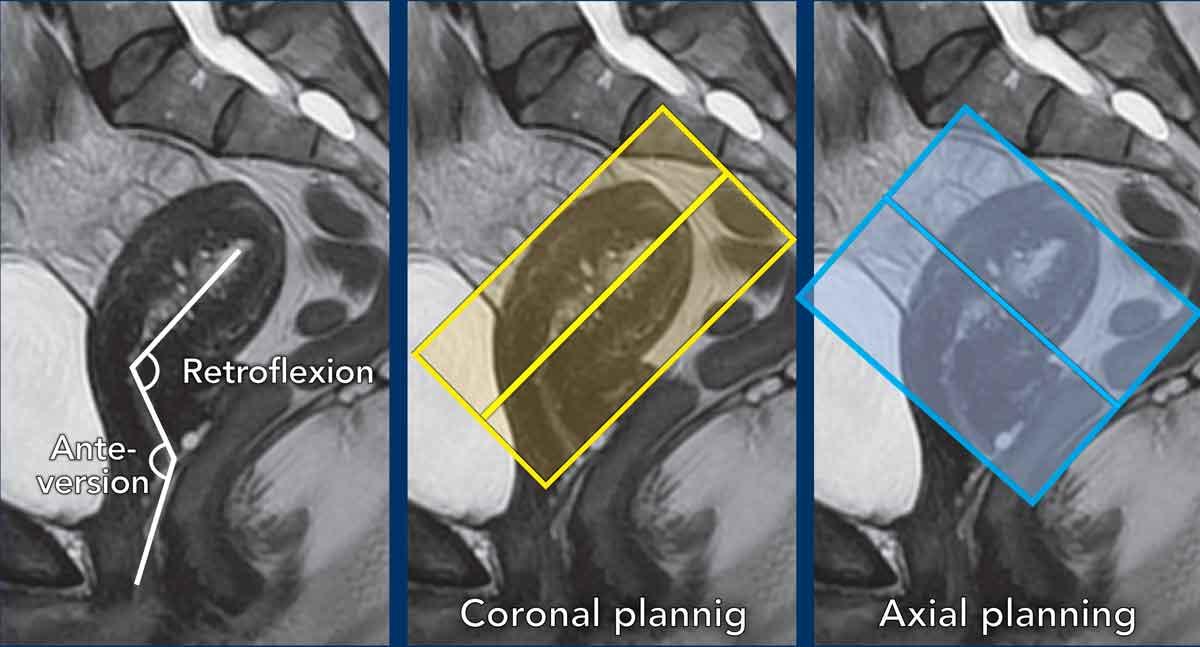

Lập kế hoạch chuỗi xung

Các chuỗi xung MRI được lập kế hoạch dựa trên trục dài của buồng tử cung.

Mặt phẳng trục vuông góc với trục dài của buồng tử cung.

Mặt phẳng vành song song với trục dài.

Lưu ý: các biến thể trong giải phẫu tử cung

Cần tính đến vị trí của tử cung và lập kế hoạch các chuỗi xung MRI vuông góc và song song tương ứng.

Trong trường hợp này, cổ tử cung ở tư thế ngả trước và thân tử cung ở tư thế gập sau.

Chuỗi ảnh mặt phẳng vành được lập kế hoạch song song với buồng tử cung (ô vàng), trong khi chuỗi ảnh mặt phẳng trục được lập kế hoạch vuông góc với nó (ô xanh lam).

Đây là một ví dụ khác cho thấy cổ tử cung ở tư thế ngả sau và thân tử cung ở tư thế gập trước.

Hãy quan sát cách biến thể vị trí này ảnh hưởng đến việc lập kế hoạch chuỗi xung tương ứng.